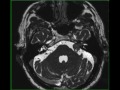

Vestibular Schwannoma, left

38-year-old male with left sided hearing loss. There is a T1-isointense, T2/FLAIR mildly hyperintense mass centered within the left internal auditory canal, spilling into the left cerebellopontine angle. There is a small cystic component of the lesion at the left CPA. There is mild diffusion restriction and avid enhancement. The findings are compatible with a left-sided vestibular schwannoma. Vestibular schwannoma is a benign tumor arising from Schwann cells that wrap the vestibulocochlear nerve. Differential diagnosis includes meningioma, epidermoid, and metastasis. The presence of bilateral vestibular schwannoma should raise suspicion for neurofibromatosis type 2.